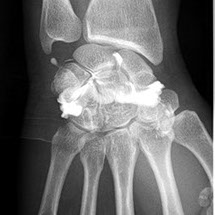

Cet examen consiste à injecter à l’aide d’une aiguille, sous guidage radiologique un produit de contraste iodé à l’intérieur d’une articulation. Les articulations concernées sont variées : genou, cheville, épaule, coude, poignet, hanche.

L’arthrographie est généralement immédiatement complétée par un scanner de l’articulation (arthroscanner). Ceci ne nécessitera pas de deuxième piqûre.

L’arthrographie, généralement couplée à l’arthroscanner permet au radiologue d’établir un diagnostic précis sur l’état des cartilages de l’articulation concernée, de déceler des ruptures partielles ou complètes des tendons, des ligaments, ou encore de déceler des corps étrangers au sein des articulations explorées. Cette exploration peut être couplée à une infiltration dans le même temps opératoire.